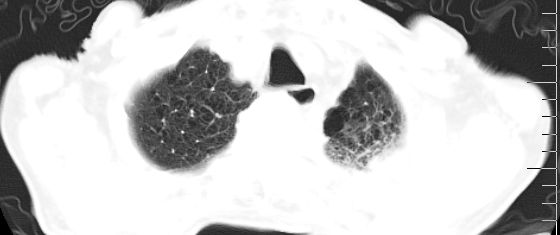

标题: CT10141:男、84岁,咳嗽、咯血1年。 [打印本页]

标题: CT10141:男、84岁,咳嗽、咯血1年。

支持左侧中央型肺癌伴下叶肺不张\\纵隔淋巴结转移.左侧包裹性胸腔积液\\心包积液.左侧少量胸腔积液..慢性支气管炎伴部分间质纤维化.

支持:左侧中央型肺癌伴下叶肺不张\\纵隔淋巴结转移.左侧包裹性胸腔积液\\心包积液.左侧少量胸腔积液..慢性支气管炎伴部分间质纤维化.另:支气管分支根部明显阻塞 狭窄,内膜凸凹不平,提示内膜增生物。

咯血病史较长,左肺下叶实变,体积未明显缩小,隐约可见血管影及坏死阴影,双肺门及纵隔淋巴结增大,心包增厚积液,纵隔右移位,单侧胸腔积液,首先考虑:大叶型肺泡癌伴纵隔心包转移。

左肺中心性肺癌并左肺下叶肺不张,纵隔淋巴转移、同侧胸腔及心包积液(转移)。